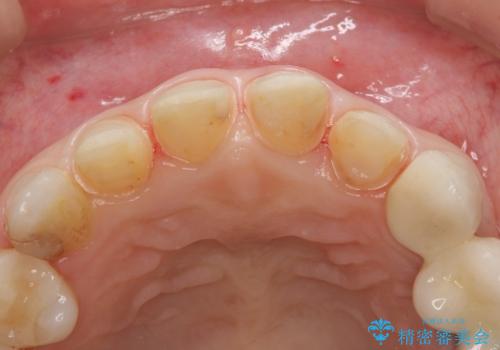

- 保険治療のプラスチックでつぎはぎの歯をセラミックにし、一緒に前歯の並びもきれいにしたいとのご希望でした。

神経を温存するようにあまり削らないように治療しました。

- 51.7万円(ジルコニアクラウンスタンダード 10万円x4本、仮歯1万円x4本 オフィスホワイトニングエクセレント 3万円x1回)費用は治療当時の料金となります